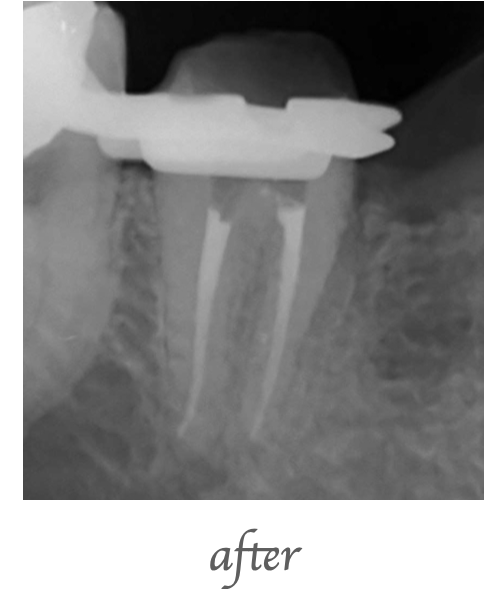

右上奥歯にインプラントを希望して来院されました。他院では骨がないためインプラントは出来ないと言われたとのことでしたが、サイナスリフト(上顎洞底挙上術)を行うことで骨の高さが3mmから14mmまで増加しました。

治療回数:サイナスリフトは一度の手術で終わります。その後インプラントの手術が必要になります。

治療期間:サイナスリフトを行いしっかりした骨が出来るのは約6ヶ月かかります。その後にインプラント治療を行います。

サイナスリフト:¥200,000(税込220,000)

上顎洞底の粘膜を持ち上げて、そこに骨を作る手術になります。粘膜は1mm程度の薄い膜のため持ち上げる際に穿孔(穴が開く)する場合があります。小さい穴であれば閉鎖することが出来ますが、大きな穴が開くと再度手術になる場合があります。術後に腫れ、痛み、出血、感染のリスクがあります。